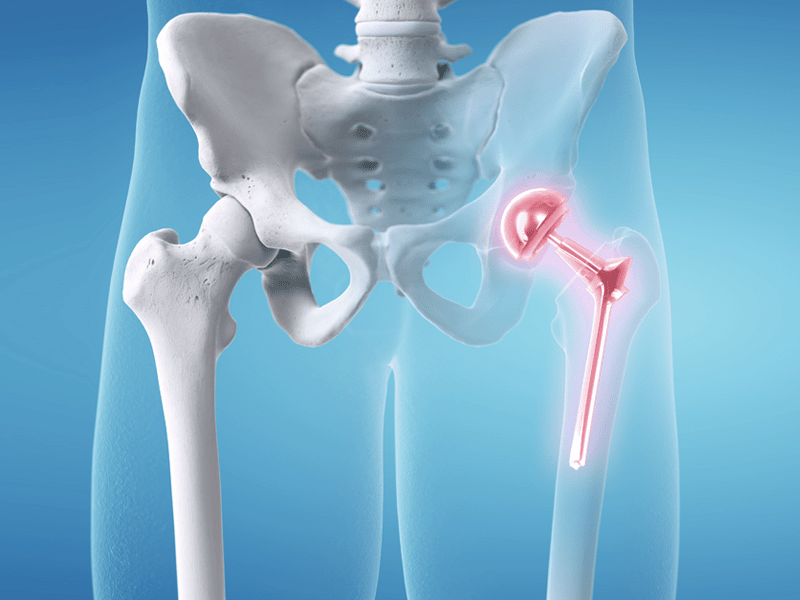

جراحی تعویض مفصل لگن یکی از پیشرفتهترین و مؤثرترین روشهای درمانی برای بهبود کیفیت زندگی بیمارانی است که از دردهای شدید و محدودیتهای حرکتی ناشی از آسیبهای مفصل لگن رنج میبرند. این جراحی به ویژه برای بیمارانی که به آرتروز شدید یا شکستگیهای مفصل لگن دچار شدهاند، تجویز میشود. در این مقاله به بررسی جامع […]

تعویض مفصل لگن (Hip Replacement Surgery) یکی از موفقترین جراحیهای ارتوپدی برای کاهش درد و بهبود کیفیت زندگی بیماران مبتلا به آرتروز، نکروز استخوانی یا شکستگیهای شدید لگن است. اما موفقیت نهایی این جراحی، تنها به عمل محدود نمیشود؛ بلکه توانبخشی و راه رفتن صحیح پس از تعویض مفصل لگن نقش حیاتی در بازگشت بیمار […]